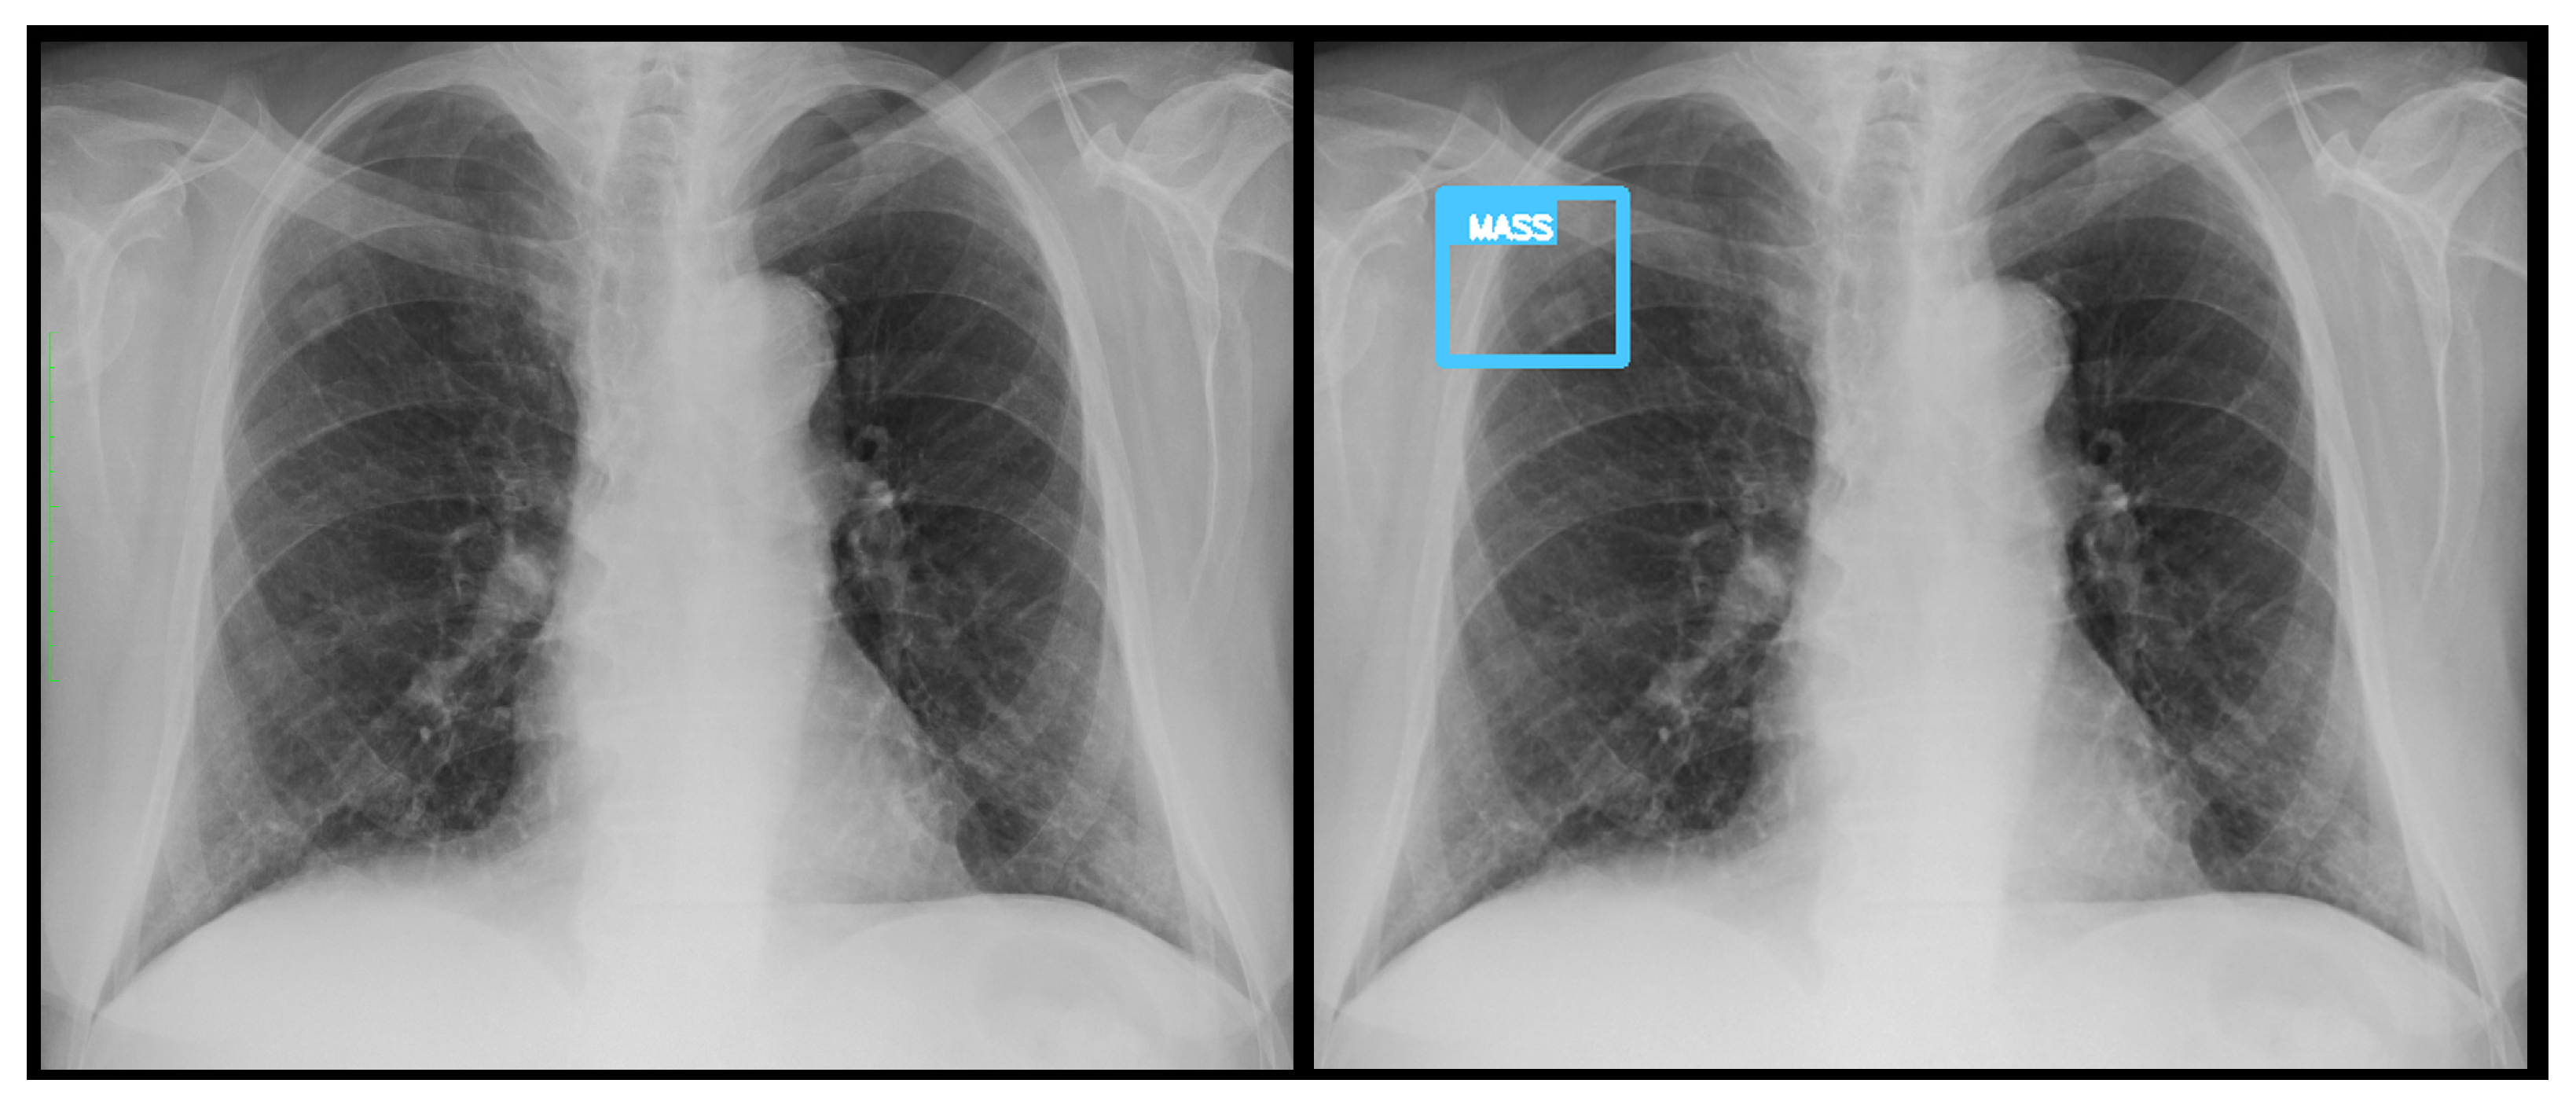

Figure 11. A false negative example of a missed loculated pneumothorax. The presence of pulmonary markings (black arrow) beyond the pleural line (white arrowhead) may have misled the algorithm.

3.3. Error Analysis

An analysis of the algorithm’s false negatives revealed a nuanced performance profile, where a specific miss did not always equate to a complete system failure. Across the board, a substantial number of cases with a false negative for a particular pathology were nevertheless correctly identified as abnormal by the general “yes-finding” classifier or had other co-occurring true positive pathologies. For example, out of 38 false negatives for opacity, the algorithm correctly identified the exam as abnormal in 25 cases. In many instances of a missed finding, the algorithm successfully detected other pathologies within the same study. Misclassification was another notable source of error, where an existing pathology was detected but incorrectly labeled, such as opacities being predicted as masses or nodules (Figure 4). Radiologist review of these false-negative cases frequently noted findings that were “subtle,” “small,” “doubtful,” “seen on lateral image only,” or “non-specific.” In other cases, the algorithm correctly identified a more critical finding, like a large pleural effusion, while missing a secondary, less significant pathology (Figure 3). Figure 9, Figure 10 and Figure 11 illustrate false negative cases for opacity, pneumothorax, and nodule, respectively. This highlights the inherent limitations and inevitable failures of this kind of system.